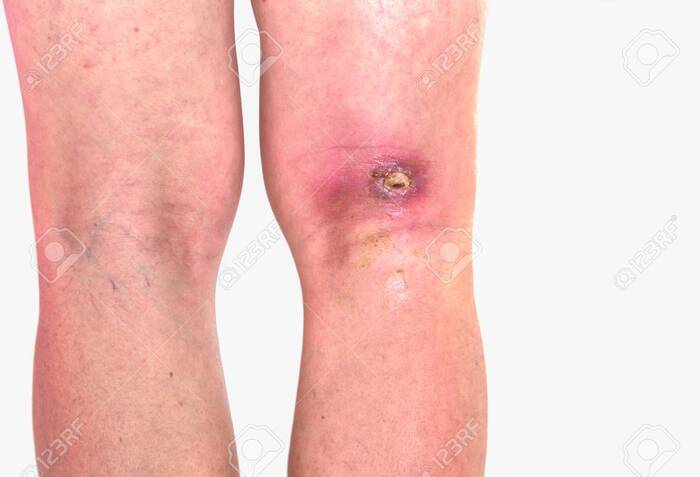

- абсцесс - инфекционное воспаление мягких тканей, как правило предшествует травматизация (порез, прокол, сглаз), сопровождается признаками интоксикации - повышение температуры тела, озноб, слабость.

Лечение хирургическое.